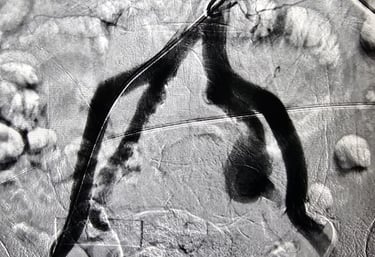

Galería

Imágenes de nuestros tratamientos en angiología y cirugía vascular.